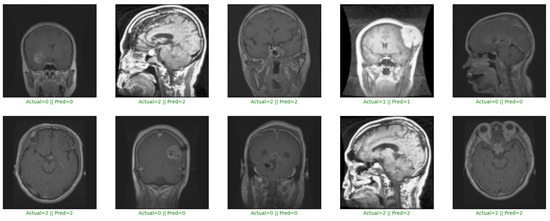

A salient feature of our model is its high precision, which measures its ability to make accurate positive predictions. Across all three datasets, our model consistently achieved precision rates that underline its ability to accurately identify brain tumors. For instance, on Dataset 2, our model attained a precision rate of 98.81% (as shown in Table 5), outperforming other models such as VGG16, VGG19, and MobileNet by margins of 0.88%, 2.37%, and 1.48% (as shown in Table 5). Precision is critical in medical diagnoses, ensuring reliable positive predictions and minimizing false positives (as shown in Figure 4), which can lead to unnecessary interventions and patient anxiety. The consistently high precision rate of our model across datasets underscores its suitability for clinical applications.

Figure 4.

Multi-modal brain tumor detection and classification on Dataset 2.